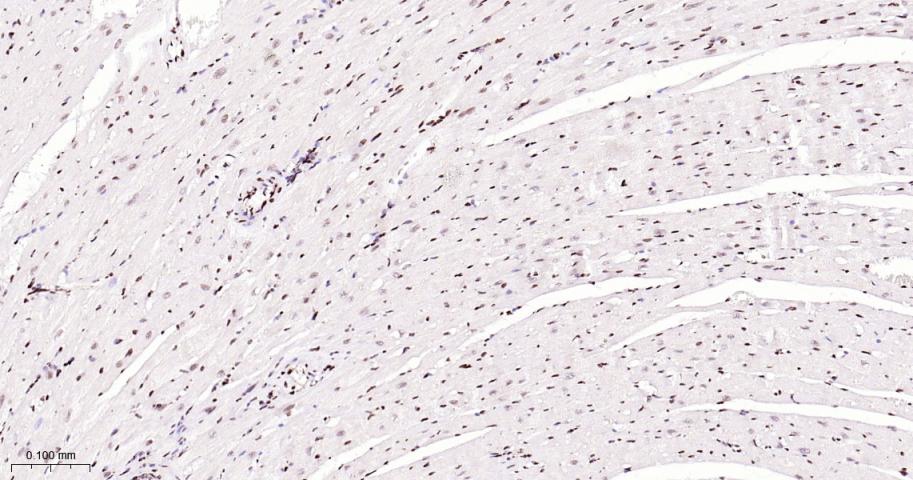

Paraformaldehyde-fixed, paraffin embedded Mouse Heart; Antigen retrieval by boiling in sodium citrate buffer (pH6.0) for 15 min; The section was incubated with CTBP2  Monoclonal Antibody, Unconjugated (bsm-62448R) at 1:200 overnight at 4°C, followed by conjugation to the bs-0295G-HRP and DAB (C-0010) staining.